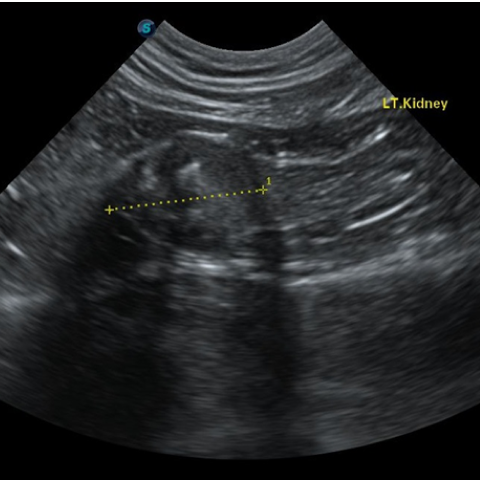

´Ù³¶¼º½ÅÀ庴

(PKD, Polycystic Kidney Disease)(Triaditis)

´Ù³¶¼º½ÅÀ庴À̶õ, ½ÅÀå¿¡ ´Ù¼öÀÇ ³¶Á¾ÀÌ ¹ß»ýÇϰí ÀÌ·Î ÀÎÇØ ½ÅÀå ±â´ÉÀÌ ÀúÇÏµÇ¸é¼ ¼¼È÷ ¸¸¼º ½ÅºÎÀüÀ¸·Î ÁøÇàµÇ´Â ÁúȯÀÔ´Ï´Ù. ÁÖ·Î Æä¸£½Ã¾È, È÷¸»¶ó¾á °°Àº ´ÜµÎÁ¾ °í¾çÀ̵鿡°Ô¼ ³ªÅ¸³ª´Â À¯Àüº´ÀÇ ÇϳªÀ̸ç, ´Ù³¶¼º½ÅÀåÀ» °¡Áø °í¾çÀ̵éÀº Æò±Õ 4¼¼¿¡ ÀÌ¹Ì ½ÅÀå ±â´ÉÀÌ ¼Õ»óµÇ±â ½ÃÀÛÇÑ´Ù°í º¸°íµÇ°í ÀÖ½À´Ï´Ù. µû¶ó¼ ÀÌ·¯ÇÑ Á¾·ùÀÇ °í¾çÀ̵éÀÇ °æ¿ì ºñ±³Àû ¾î¸° ¿¬·ÉºÎÅÍ Áö¼ÓÀûÀ¸·Î ½ÅÀå ±â´ÉÀ» ¸ð´ÏÅ͸µ ÇÏ´Â °ÍÀÌ ÇÊ¿äÇÕ´Ï´Ù. ¶ÇÇÑ ½ÅÀå »Ó ¾Æ´Ï¶ó ÁÖº¯ Àå±âÀÎ ºñÀå, °£, ÃéÀå¿¡µµ ³¶Á¾ÀÌ »ý±â¸é¼ À̵é Àå±âµµ ¹®Á¦°¡ µÉ ¼ö ÀÖÀ¸¹Ç·Î Á¤±âÀûÀÎ °Ç°°ËÁøÀ» ÅëÇØ °í¾çÀÌÀÇ °Ç° »óŸ¦ È®ÀÎÇÏ´Â °ÍÀÌ ÁÁ½À´Ï´Ù.